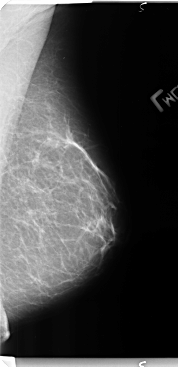

B_3136_1.LEFT_MLO

LEFT_MLO LINES 4760 PIXELS_PER_LINE 2304 BITS_PER_PIXEL 12 RESOLUTION 50 NON_OVERLAY